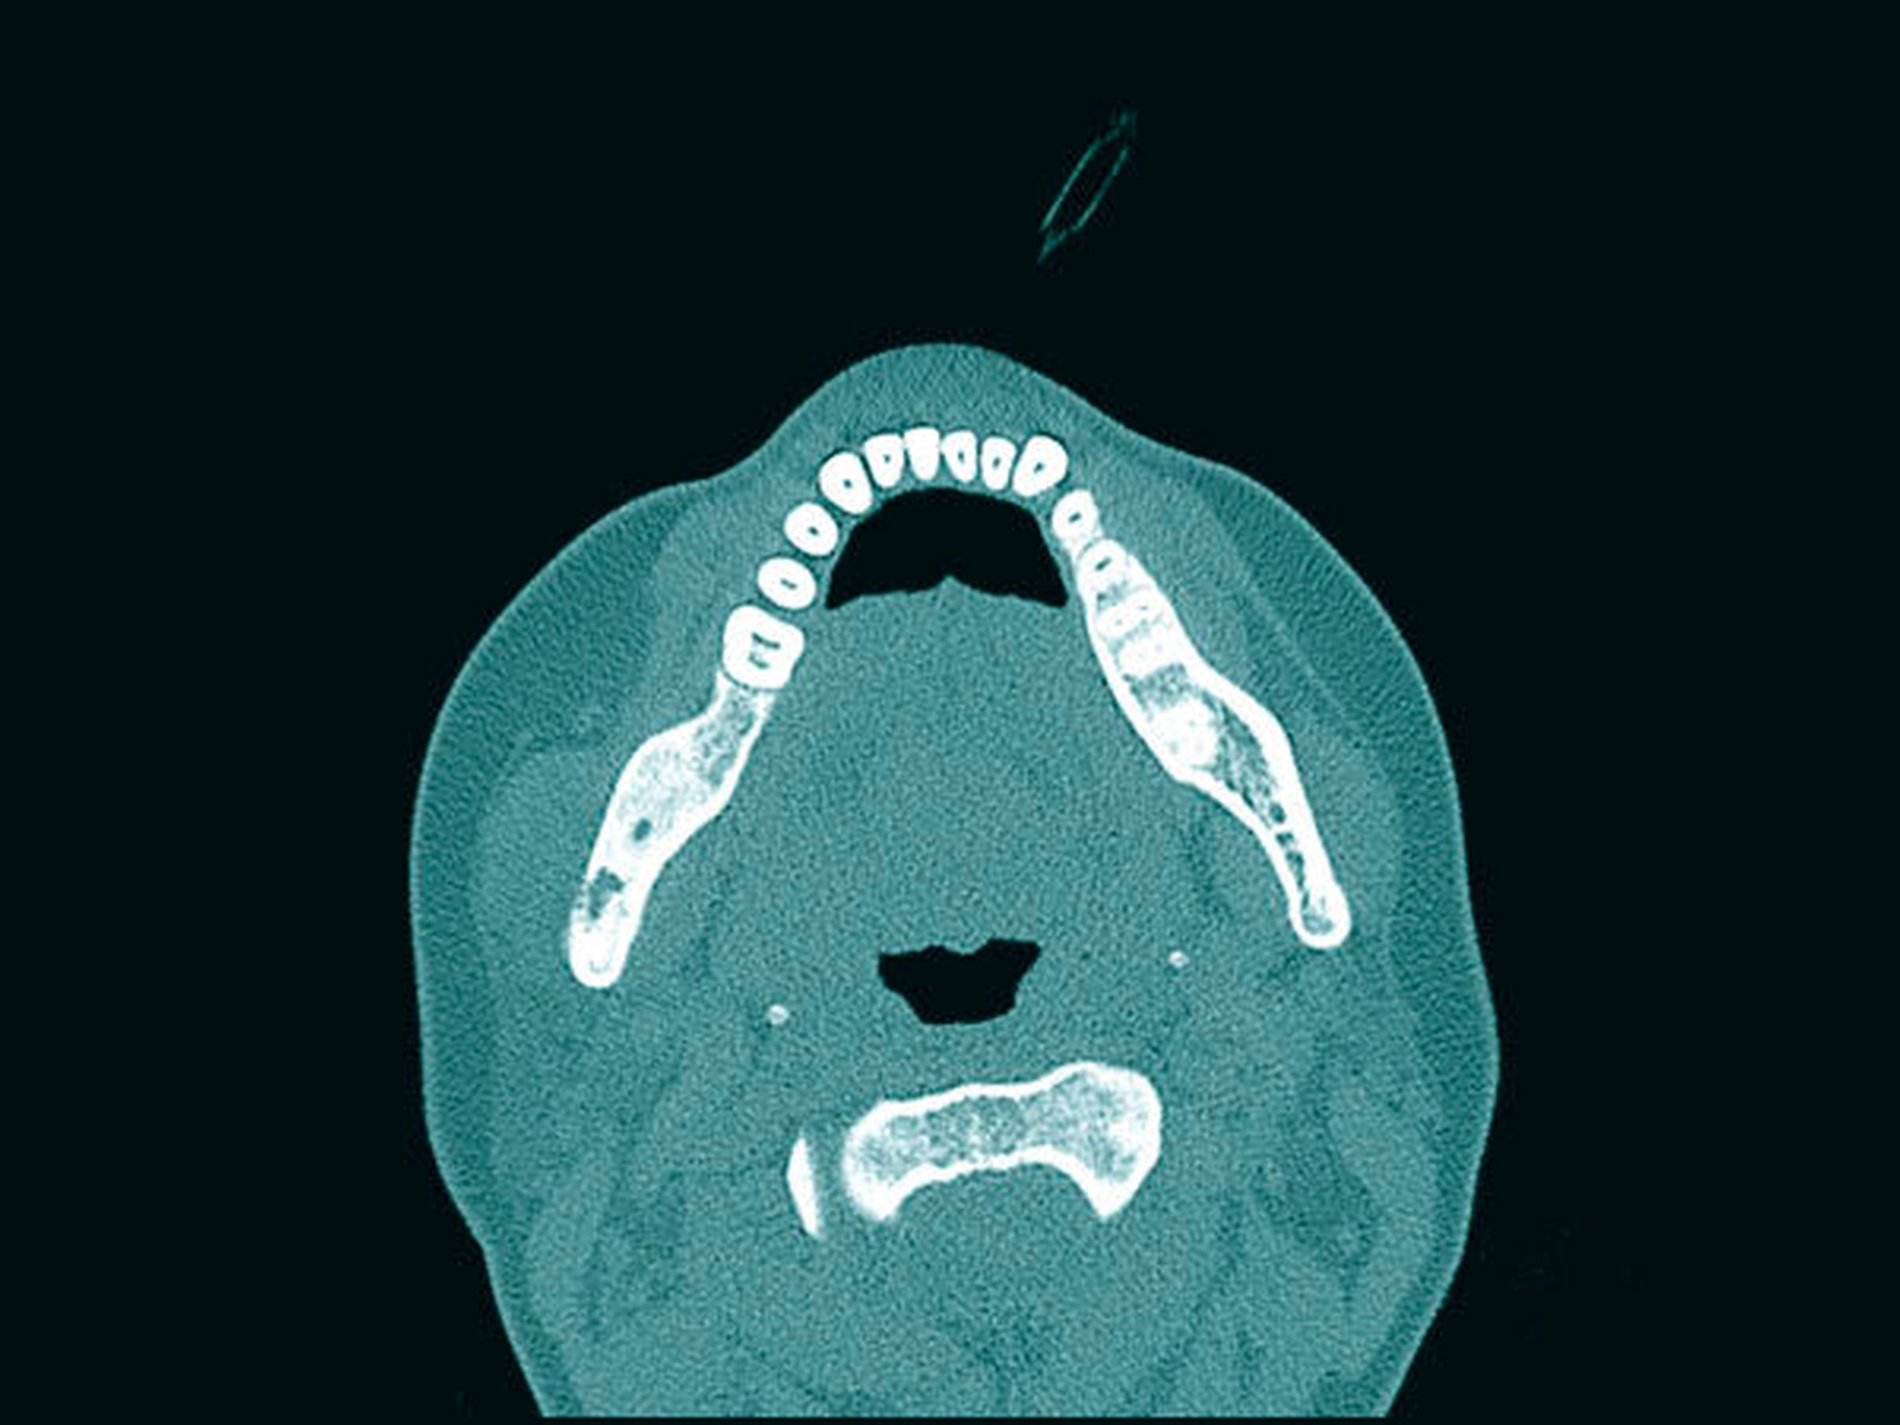

Aufgrund einer erneuten starken Zunahme der Beschwerden 2018 war der Leidensdruck der Patientin nach drei Jahren nun so groß, dass sie nach Bestätigung der erneuten Aktivitätszunahmen im Bereich des Capitulums in der Knochenszintigrafie und einer erneuten Osteolyse und in der CT im Bereich des aufsteigenden Unterkieferastes rechts und des Capitulums die Planung eines total-endoprothetischen Kiefergelenkersatzes wünschte (Abbildungen 8a bis 8c).

Dieser erfolgte nach Planung einer individuell angefertigten Gelenkprothese mit Resektion des rechten Rest-Caputs, des Collums und des Unterkiefers bis regio 44. Aus Gewichtsgründen wurde hier eine Titanlegierung verwendet und die Platte bis regio 34, 35 extendiert, um bei einer möglichen Progression der Osteomyelitis noch weitere Resektionsmöglichkeiten zu haben (Abbildung 9). Der Eingriff verlief komplikationslos und im weiteren postoperativen Verlauf berichtete die Patientin lediglich über Wärmesensationen und leichte Schwellungen.